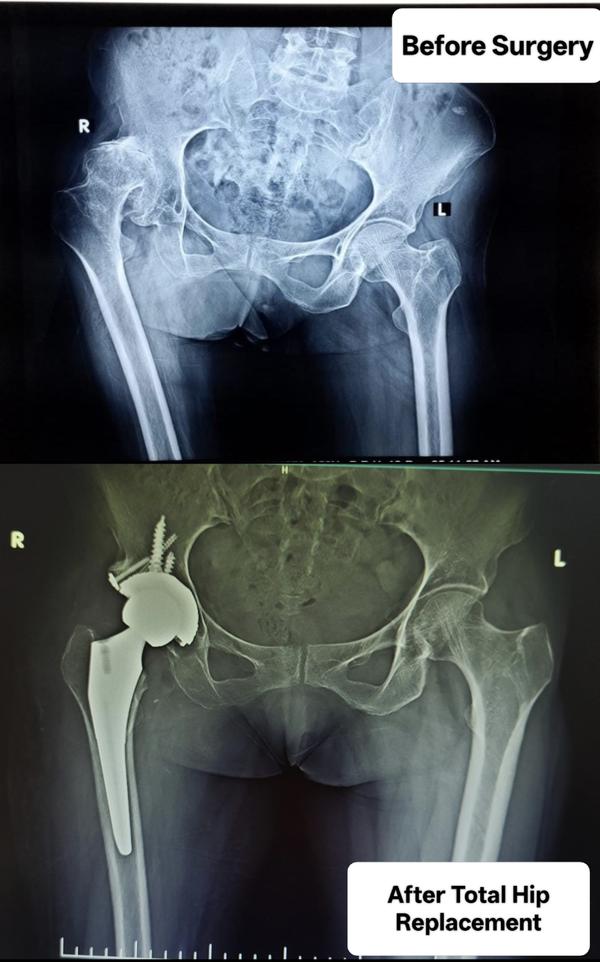

Your hips play a crucial role in your daily life, and when arthritis or a hip injury strikes, it can hinder your ability to perform everyday tasks. Severe hip pain, especially while sitting or trying to sleep, can significantly impact your quality of life. In such cases, a Total Hip Replacement may be the most viable option to alleviate pain and restore your normal activities.If you and your healthcare provider determine that a total hip replacement is the best course of action for your condition, the following information will help you gain a better understanding of what to anticipate. Total hip replacement surgery entails the removal of damaged bone within the hip joint and its replacement with a prosthetic implant. This artificial joint, also referred to as a prosthesis, not only prevents bone-on-bone contact but also re-establishes a smooth and pain-free hip joint.